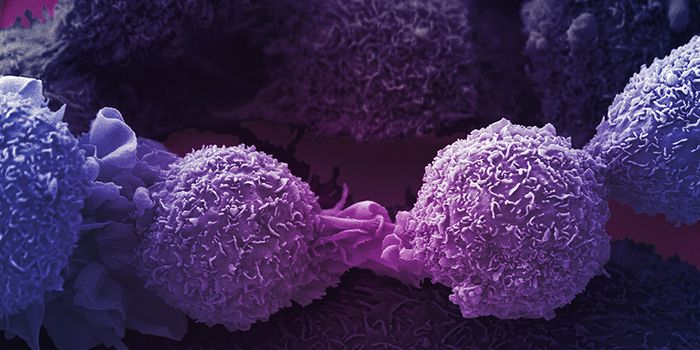

OCT 21, 2024CancerLung cancer remains a severe malignancy, expected to account for over 125,000 deaths in 2024. With high rates of m ...

DEC 07, 2021ImmunologyStrong chemical drugs used to obliterate all rapidly growing cells in the body have been used to treat cancer sin ...

FEB 26, 2018ImmunologyCancer metastasis, the spreading of tumors to different tissues in the body, is usually what makes cancer so lethal and ...

AUG 02, 2023ImmunologyCancer is a general term that encompasses different subtypes of abnormal cellular growth in different areas of the body. ...